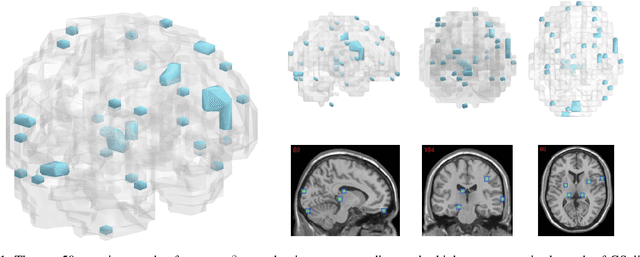

Abstract:The prediction and selection of lesion features are two important tasks in voxel-based neuroimage analysis. Existing multivariate learning models take two tasks equivalently and optimize simultaneously. However, in addition to lesion features, we observe that there is another type of feature, which is commonly introduced during the procedure of preprocessing steps, which can improve the prediction result. We call such a type of feature as procedural bias. Therefore, in this paper, we propose that the features/voxels in neuroimage data are consist of three orthogonal parts: lesion features, procedural bias, and null features. To stably select lesion features and leverage procedural bias into prediction, we propose an iterative algorithm (termed GSplit LBI) as a discretization of differential inclusion of inverse scale space, which is the combination of Variable Splitting scheme and Linearized Bregman Iteration (LBI). Specifically, with a variable the splitting term, two estimators are introduced and split apart, i.e. one is for feature selection (the sparse estimator) and the other is for prediction (the dense estimator). Implemented with Linearized Bregman Iteration (LBI), the solution path of both estimators can be returned with different sparsity levels on the sparse estimator for the selection of lesion features. Besides, the dense the estimator can additionally leverage procedural bias to further improve prediction results. To test the efficacy of our method, we conduct experiments on the simulated study and Alzheimer's Disease Neuroimaging Initiative (ADNI) database. The validity and the benefit of our model can be shown by the improvement of prediction results and the interpretability of visualized procedural bias and lesion features.

Abstract:Neuroimage analysis usually involves learning thousands or even millions of variables using only a limited number of samples. In this regard, sparse models, e.g. the lasso, are applied to select the optimal features and achieve high diagnosis accuracy. The lasso, however, usually results in independent unstable features. Stability, a manifest of reproducibility of statistical results subject to reasonable perturbations to data and the model, is an important focus in statistics, especially in the analysis of high dimensional data. In this paper, we explore a nonnegative generalized fused lasso model for stable feature selection in the diagnosis of Alzheimer's disease. In addition to sparsity, our model incorporates two important pathological priors: the spatial cohesion of lesion voxels and the positive correlation between the features and the disease labels. To optimize the model, we propose an efficient algorithm by proving a novel link between total variation and fast network flow algorithms via conic duality. Experiments show that the proposed nonnegative model performs much better in exploring the intrinsic structure of data via selecting stable features compared with other state-of-the-arts.